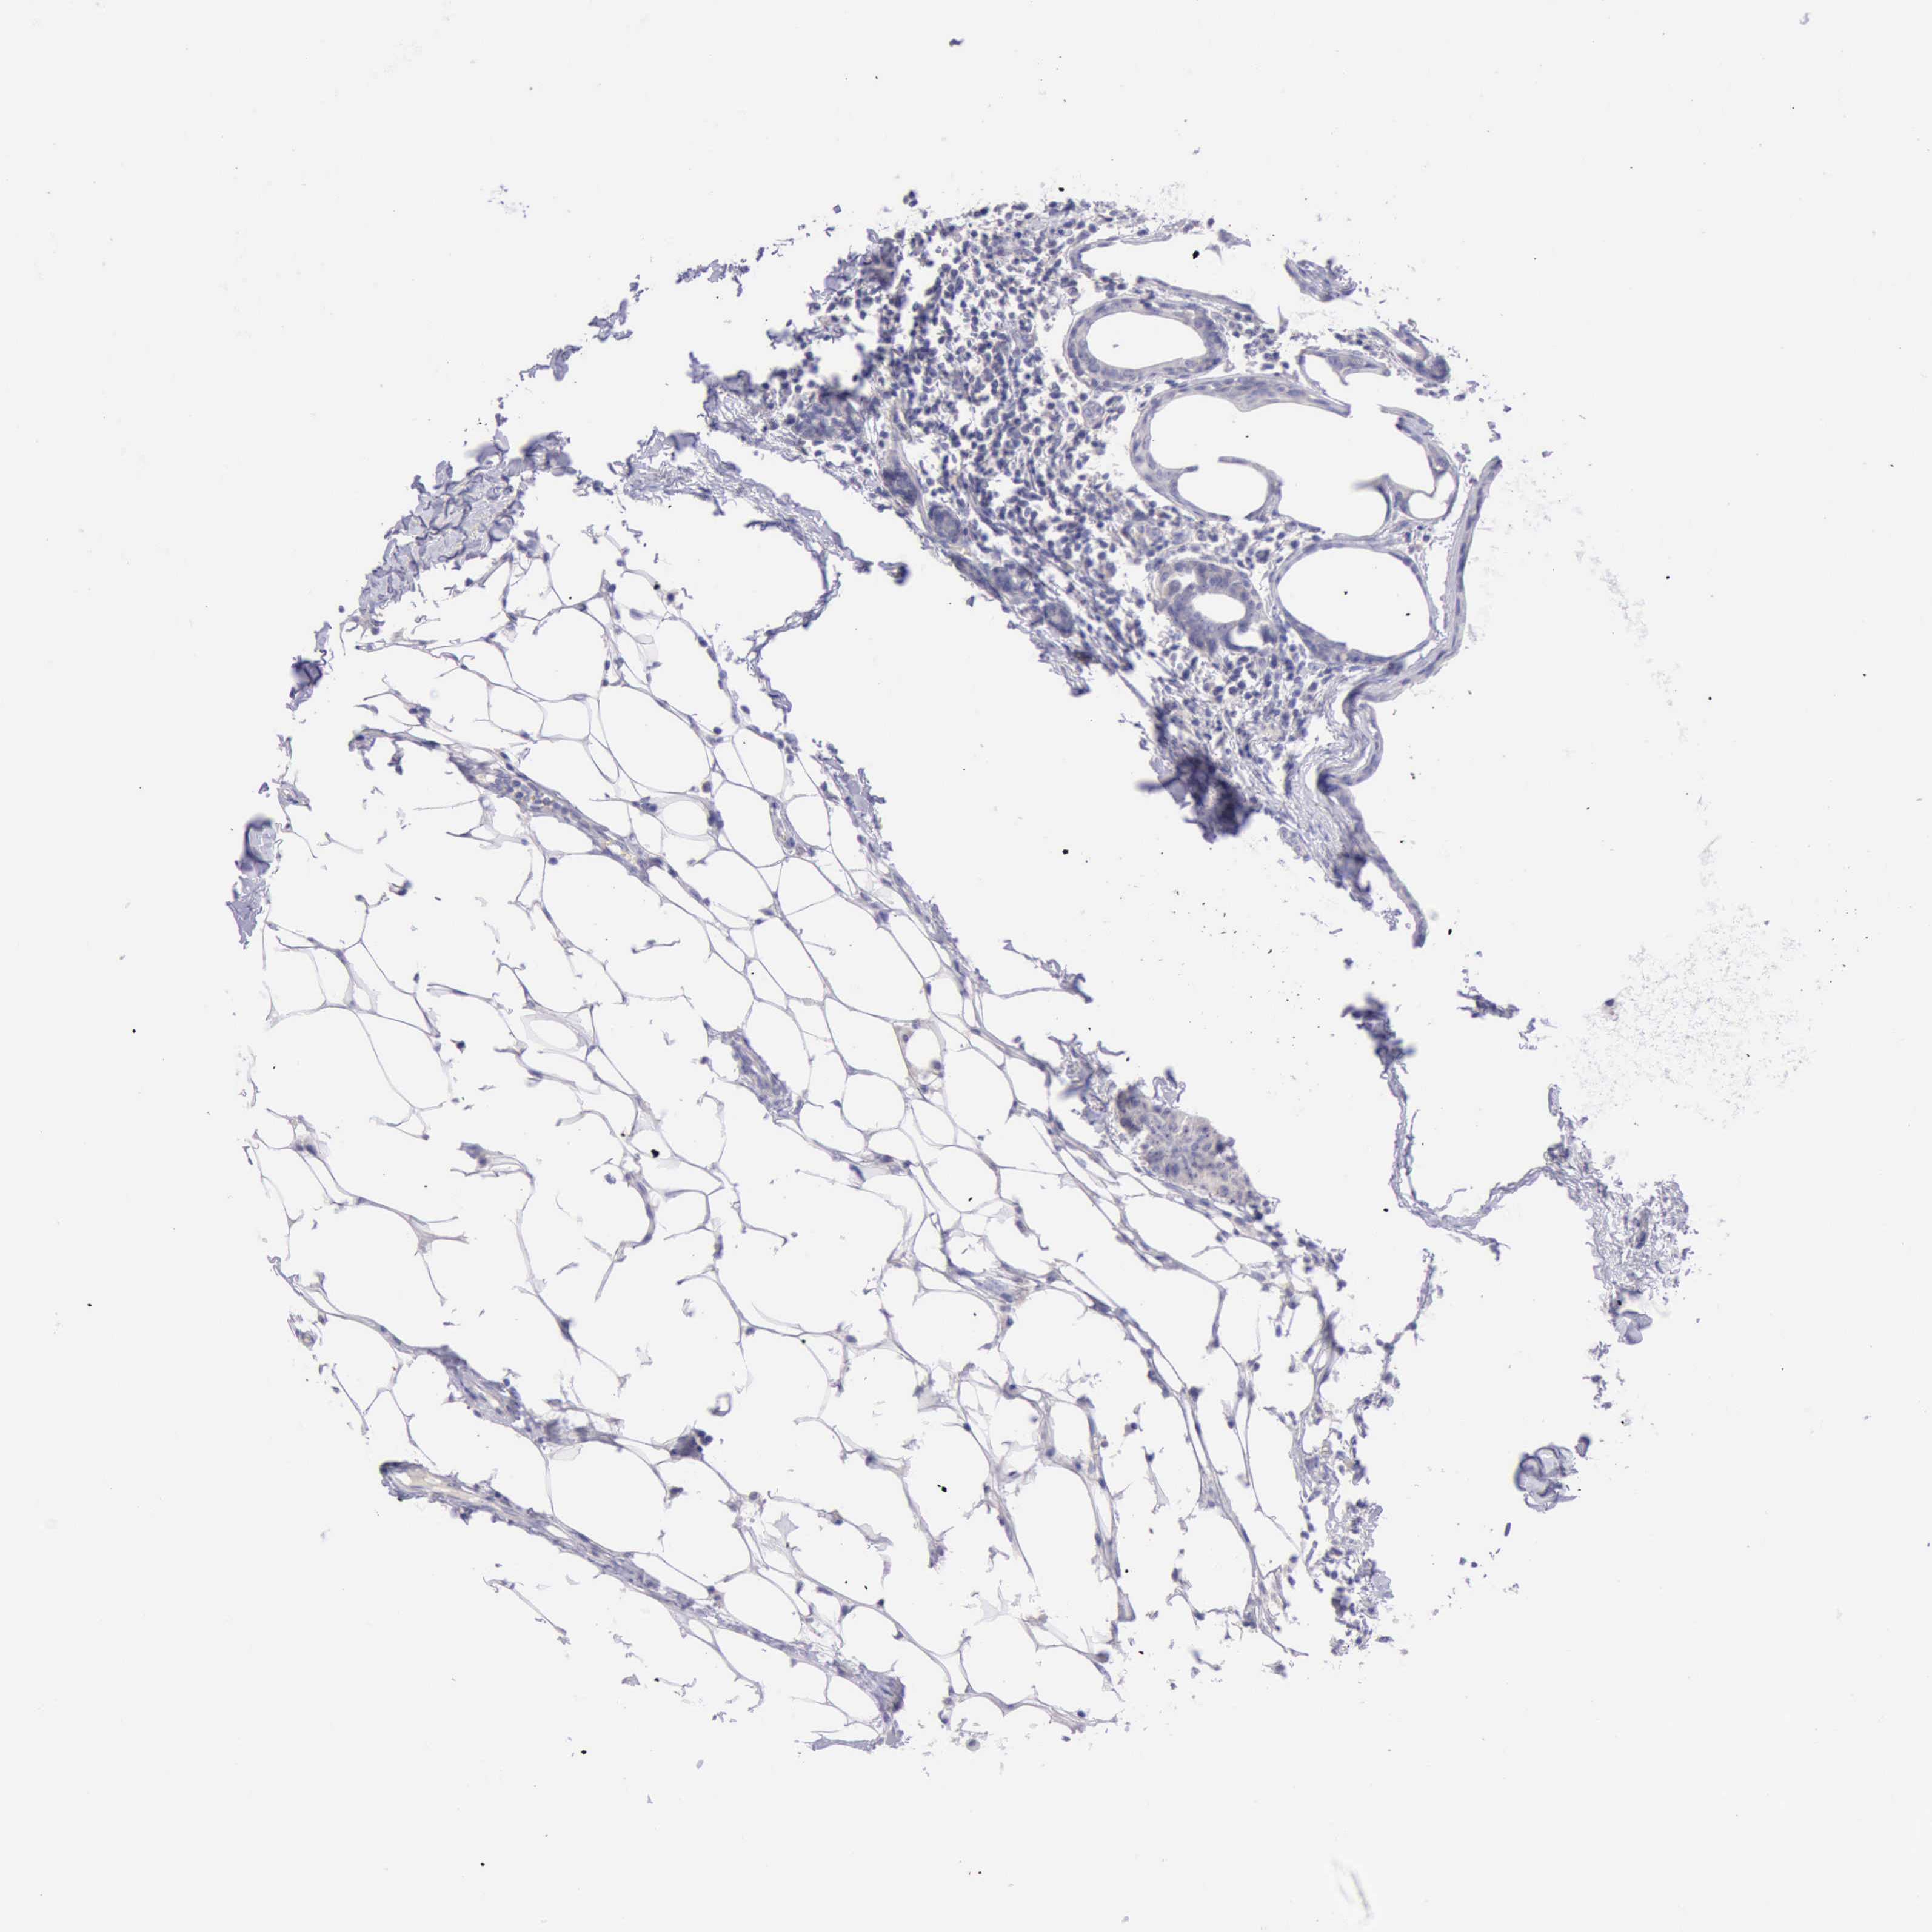

BRCA TCGA BRCA VALIDATION PROTEIN EXPRESSION

Breast cancer

Human cancer